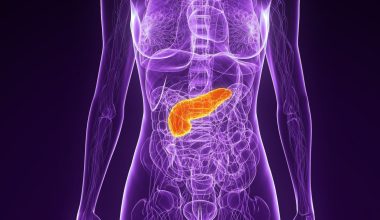

Η αποφρακτική βρογχιολίτιδα, ή αλλιώς ο «πνεύμονας ποπ κορν» συμβαίνει όταν οι μικρότεροι αεραγωγοί στους πνεύμονες, παθαίνουν φλεγμονή και δημιουργούνται ουλές.

Η βλάβη στα βρογχιόλια διαταράσσει την κανονική ροή αέρα μέσα και έξω από τους πνεύμονες, οδηγώντας σε συμπτώματα, όπως δύσπνοια, ξηρό βήχα και συριγμό.

Αυτά τα συμπτώματα συχνά επιδεινώνονται με την άσκηση ή τις σωματικές δραστηριότητες.

Τα συμπτώματα του πνεύμονα ποπ κορν αναπτύσσονται σταδιακά μέσα σε εβδομάδες ή μήνες καθώς οι αεραγωγοί στενεύουν και μειώνουν την παροχή οξυγόνου στους πνεύμονες. Με την πάροδο του χρόνου, η φλεγμονή και οι ουλές των βρογχιολίων μπορεί να επιδεινωθούν, καθιστώντας την αναπνοή όλο και πιο δύσκολη.

Η έγκαιρη διάγνωση και θεραπεία του πνεύμονα ποπ κορν μπορεί να βοηθήσει στην επιβράδυνση της εξέλιξης της νόσου και να μειώσει τη σοβαρότητα των συμπτωμάτων, τα οποία είναι: